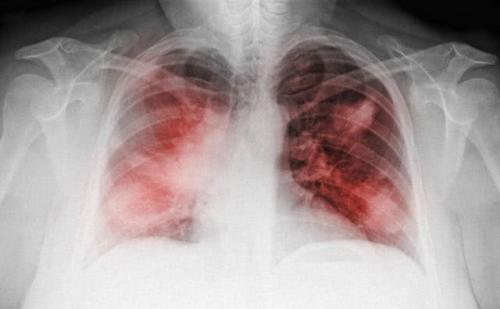

尘肺病,是由于在职业活动中长期吸入生产性粉尘(灰尘),并在肺内潴留所引起的以肺组织弥漫性纤维化为主的全身性疾病。但只要杜绝粉尘的吸入,也即做好有效呼吸防护,就可有效预防尘肺这种职业病。因此,国家要求接尘工人在车间工作时需佩戴专业的防尘口罩。专业性防尘口罩,不仅在材质上,在防尘效果上有严格的等级划分。根据我国国家标准GB2626-2006,防尘口罩过滤元件的等级依据防尘效果的不同,从低到高划分为KN90、KN95、KN100三个级别。其中KN100等级的专业防尘口罩,通过多层不同材质的滤棉层及静电吸附原理,可以有效杜绝粉尘吸入,防尘效果达到99.99%,使工人在工作时依然可以处于干净,没有粉尘污染的环境,能够安安心心上班,健健康康回家。